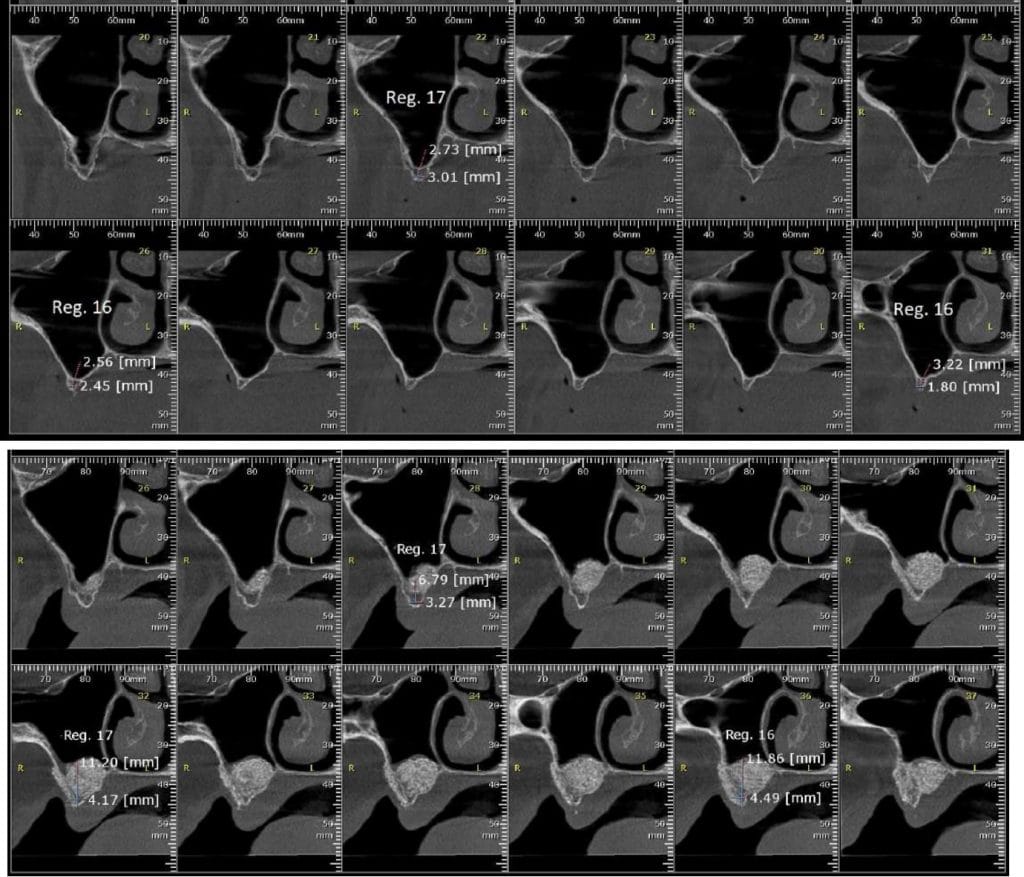

Olá colegas, aqui está um caso didático de reconstrução óssea total da maxila, levantamento do seio maxilar bilateral e bloqueio espesso com aplicação do conceito de PRF e Biotensigrity.

Após 6 meses de maturação óssea e implantes instalados com torque médio de 35 N / cm2.